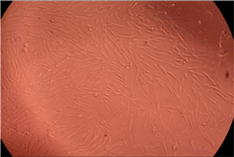

| Sample | Micrographs | ||

|---|---|---|---|

| 24 h | 48 h | ||

| Control |  |  | |

| F127 | 10 µg/mL |  |  |

| 50 µg/mL |  |  | |

| 100 µg/mL |  |  | |

| 200 µg/mL |  |  | |

| F127/PA = 10/1 (g/g) | 10 µg/mL |  |  |

| 50 µg/mL |  |  | |

| 100 µg/mL |  |  | |

| 200 µg/mL |  |  | |